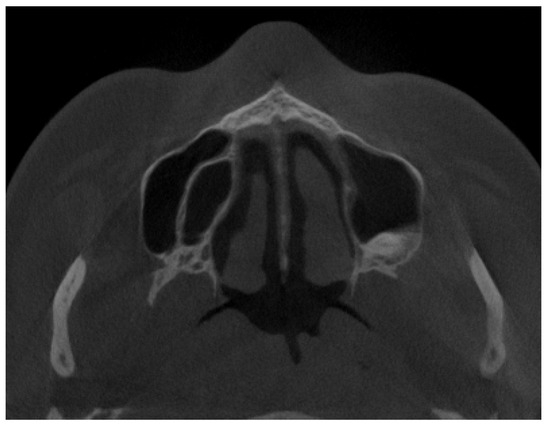

2.2. Cone Beam Computed Tomography Characteristics

2.3. Methods—Classification Proposal